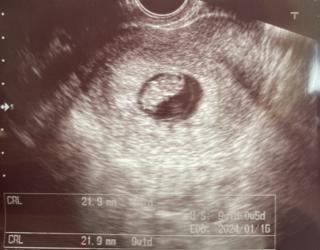

写真:8w6d:はちさん

先週まで9.3mmだったのに21.9mmに成長してくれてました。先生にも、順調といっていただけました。

不安はずっと続きますが、お腹の子を信じて頑張ります!

8w2dぐらいかと思ったら8w6d!! 初めて手も見えて、心臓も動いてました。 予定日も1/12で確定をもらえました。 看護師さんからも可愛いと言われて 先生も凄くハイテンションに喜んでくれて… 長い時間丁寧に説明してもらえました。 次の検診が楽しみです。